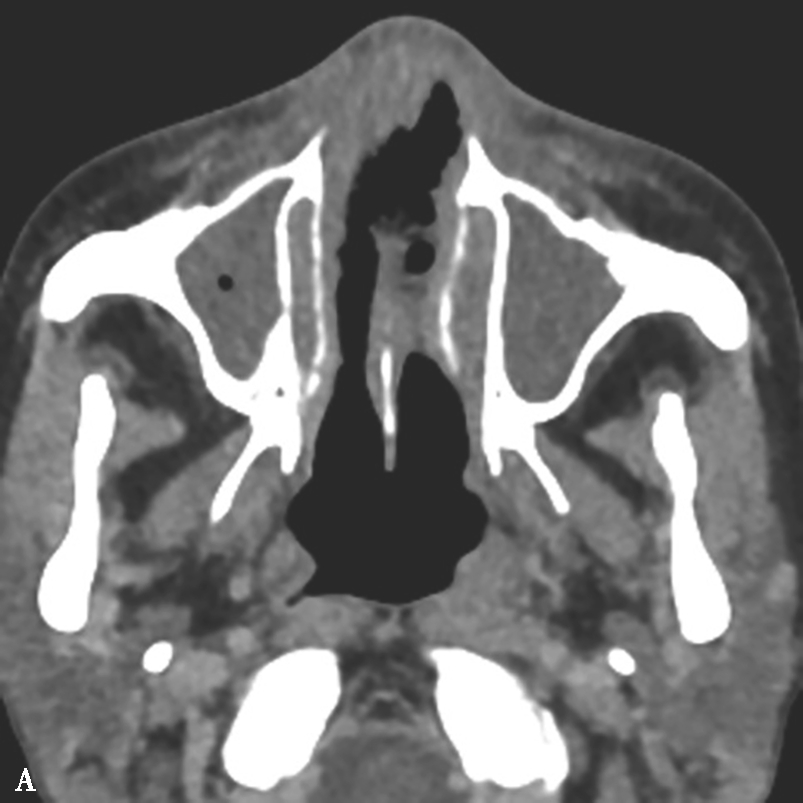

图1-3-28 鼻源性眼眶蜂窝织炎

A.横断面CT骨窗,示左侧筛窦炎,破坏左侧筛房间隔及眼眶内壁,并累及左侧眼眶内象限,注意病变内气体;B.横断面T 1 WI+FS+C,示眼眶内象限边缘强化的眶骨膜下脓肿,左侧眼眶内容物受压向前外移位,左侧眼睑增厚强化

5.CT表现

①平扫表现:眶隔前蜂窝织炎,眼睑增厚,皮下脂肪间隙模糊;眶骨膜下脓肿,眶壁下肌锥外间隙丘状肿物;眶内蜂窝织炎(图1-3-28A),眶内结构正常界面消失,眶脂体密度增高,眼球突出;球后视神经炎,视神经增粗,边缘模糊。②增强扫描表现:多呈弥漫性不均匀强化,眶骨膜下脓肿呈边缘强化或环形强化。

6.MRI表现

①T 1 WI表现:呈不均匀等、低信号;②T 2 WI表现:多呈不均匀高信号;③弥散加权像:眶骨膜下脓肿呈高信号,ADC图呈低信号;④增强扫描:呈不均匀片絮状强化,眶骨膜下脓肿呈边缘强化或环形强化(图1-3-28B)。